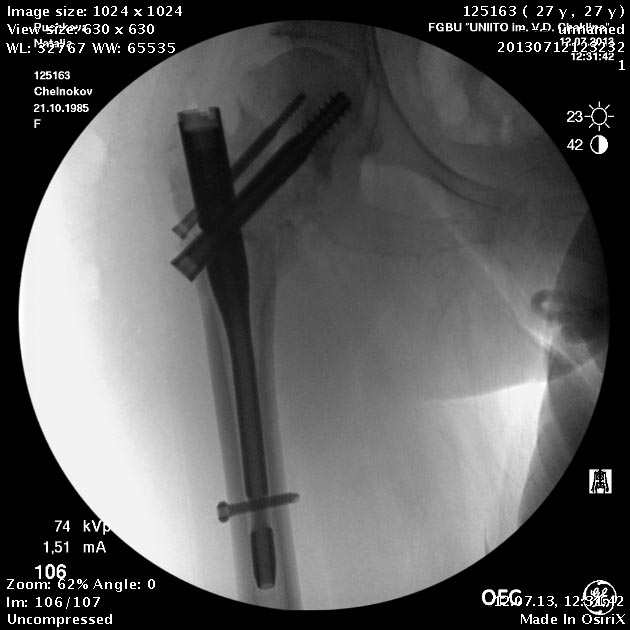

Пациентка приехала на этой неделе. Сегодня сделали правое бедро. Удалили винты, сделали чрескожную вальгизирующую остеотомию, зафиксировали Affixus. Второе бедро будем делать недели через 2.

Добрый день! Коллеги! Складывается впечатление, что вальгизация выполнена на уровне перелома шейки бедренной кости, а не в межвертельной зоне, непонятна возможность компресси в зоне перелома (винты позиционированы резьбовой частью в зоне перелома). и уж совсем не понятно статическое блокирование дистальной части штифта. С уважением Ушаков С.

Головка до и во время остеотомии была диафиксирована несколькими спицами, так что положение ее не менялось. На картинке подрисован диафиз, был он примерно там. Дистальный винт введен больше на всякий случай, чтобы дистальный конец гвоздя не болтался. А большой винт проходит через периферический отломок, так что введение динамического винта внизу ничего не дало бы.

Добрый день! неплохо было бы еще медиализировать диафиз. а проксимальный винт вероятнее всего попал в зону остеотомии, уж больно тесно.

Медиализирующая остеотомия уже история. Делали примерно такую операцию, только без иссечения клина.